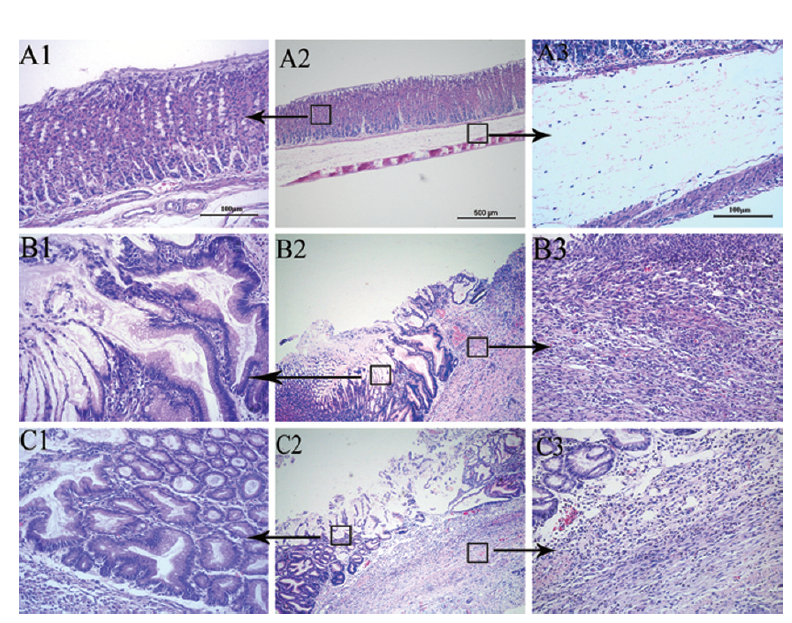

实验大鼠胃黏膜病理组织学改变(HE100×)

醋酸型胃溃疡大鼠胃组织HE 染色切片图

胃组织HE染色